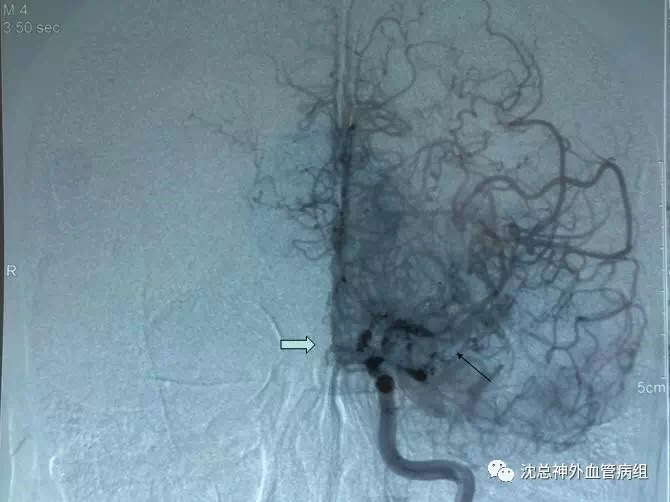

烟雾病经典手术病例分享

烟雾病影像学图片

烟雾病图片造影

烟雾病脑血管造影图片

烟雾病血管造影图

烟雾病造影图